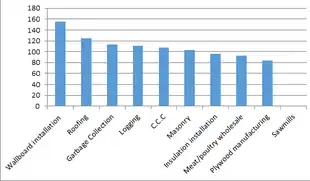

Some risk factors, such as increased age and height, cannot be changed. Increased body mass index is also associated with tearing. Recurrent lifting and overhead motions are at risk for rotator cuff injury as well. This includes jobs that involve repetitive overhead work, such as carpenters, painters, custodians, and servers.[20] People who play sports that involve overhead motions, such as swimming, water polo,[21] volleyball, baseball, and tennis, and American football quarterbacks are at a greater risk of experiencing a rotator cuff tear. Striking-based combat sports, such as boxing, also account for severe rotator cuff injuries in competitors,[22] typically when their punches miss the target, or overusing the shoulder by throwing an excessively large number of punches.[23] Certain track-and-field activities, such as shot put and javelin throw are also of considerable risk,[24] especially when athletes perform outdoors under cold weather conditions or neglect warming-up procedures; proper warm-up of the throwing and/or swinging arm can help reduce the stress on the musculature of the shoulder girdle.[25] Corticosteroid injections around the tendons increase the risk of tendon tear and delay tendon healing.[26]